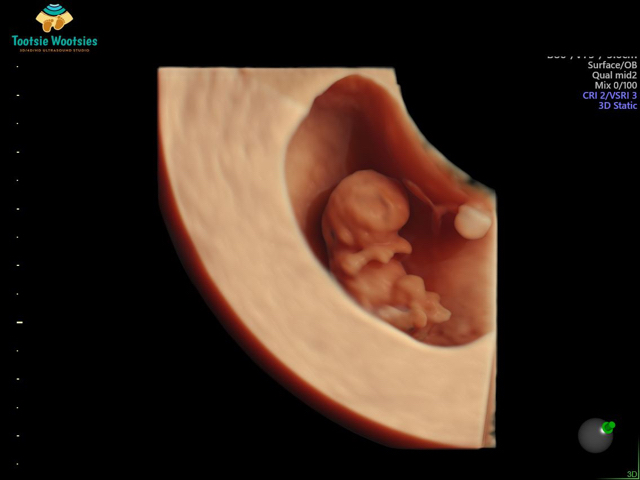

How’s baby looking? Is head okay?

Does it look like your babies? this is my rainbow after two looses..

My first baby had anencephaly (A Neural tube defect)